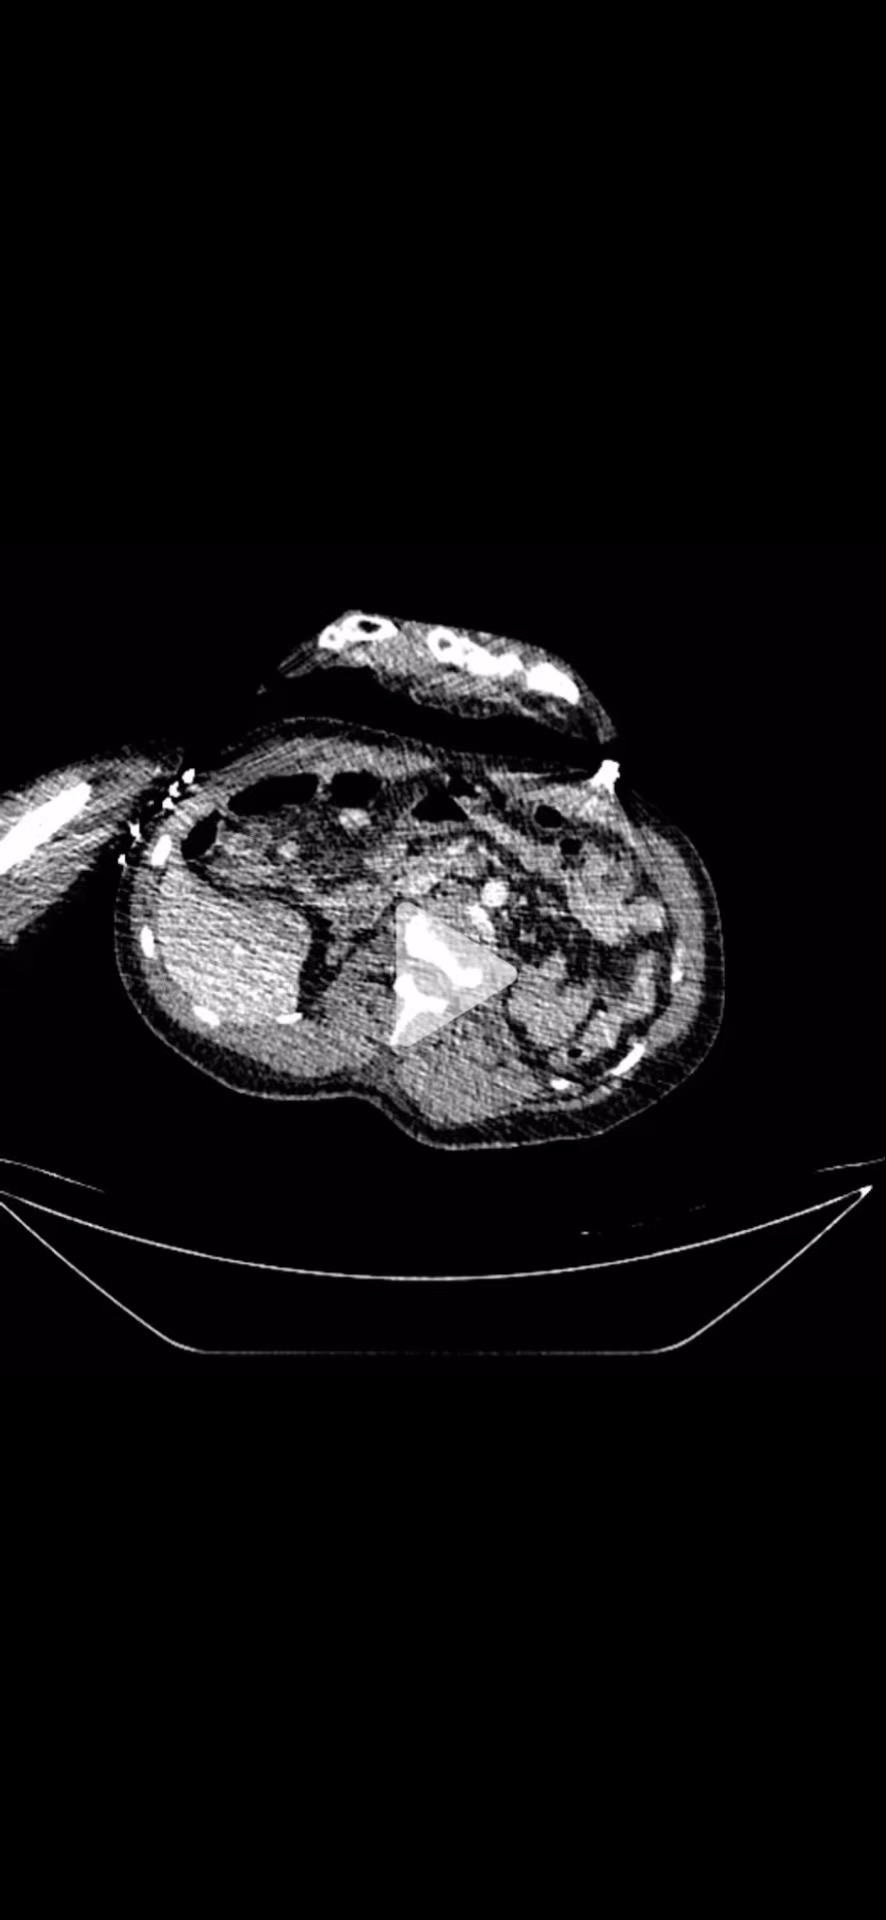

CTA静脉期: